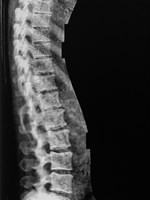

Röntgenbild av kotpelare tagen med den nya utrustningen.

Det senare, bentäthetsundersökningar, är en förutsättning för studien. Tack vare ett anslag om 1,4 miljoner kronor från Lundbergs Forskningsstiftelse finns nu en Lunar iDXA-utrustning – en röntgenapparat som ger extra högupplösta och tydliga bilder – på plats på Carlanderska. Den är snabb och effektiv samtidigt som den är lågstrålande och därmed säker för personalen. Traditionell bentäthetsmätning ger bilder på underarmar och framifrån på ländrygg och höftområde. Den nya utrustningen tar även bilder från sidan och ger en bild på hela kotpelaren som visar om patienten har kotkompression. Dessutom ger den mycket lättolkade bilder vilket enligt Jan Kilhamn har en pedagogisk poäng.

”Vi vet att om patienterna förstår och är motiverade är de också bättre på att följa rekommendationerna. Då kan de tydliga bilderna från bentäthetsmätaren göra stor skillnad. När vi kan visa att 'så här ser ditt skelett ut' kan vi också ha en informerad dialog. Visualiseringen blir ett bra verktyg.”